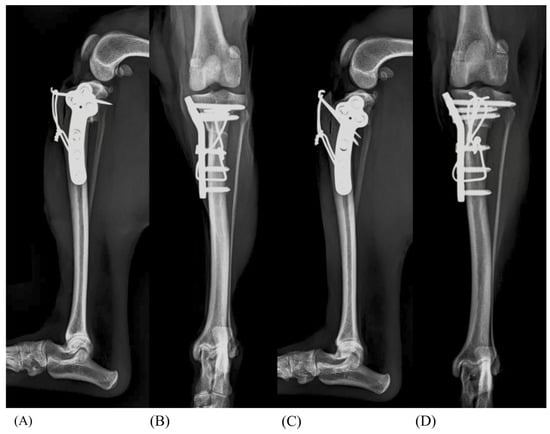

2.2. Surgical Techniques

2.3. Radiographic Measurements